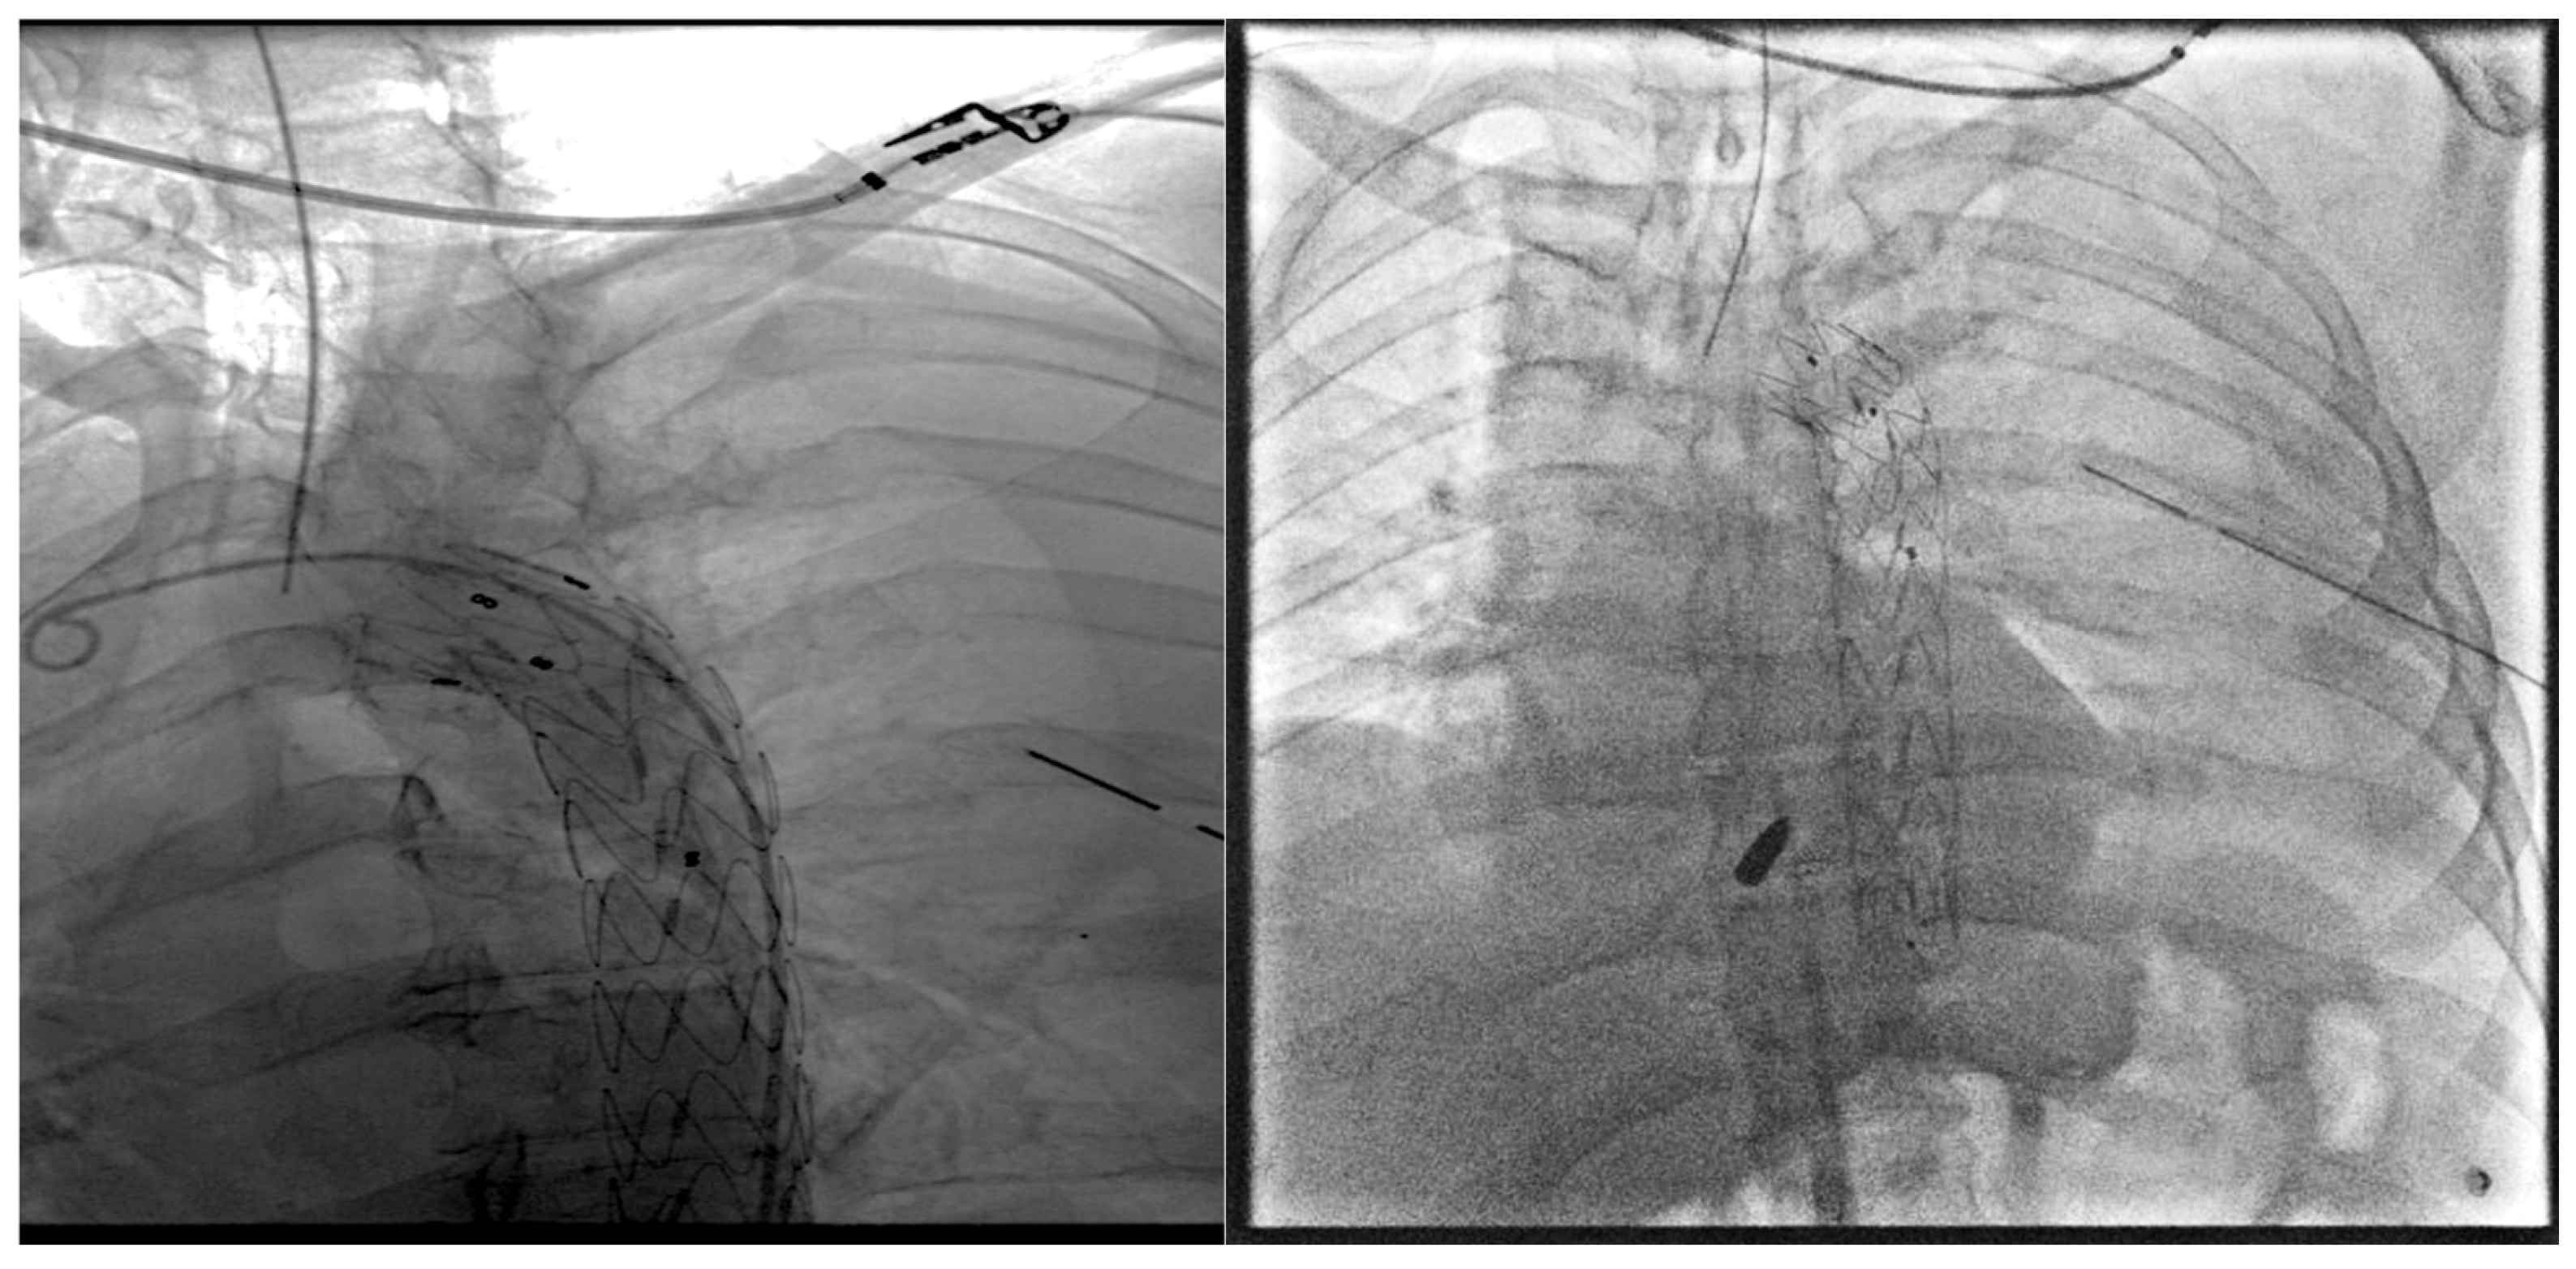

2. Case Presentation